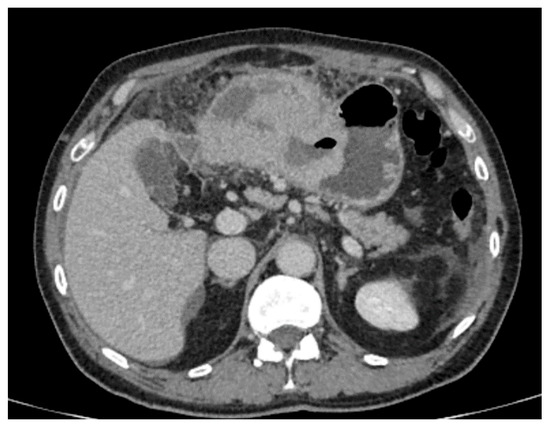

- Maximum diameter: the largest diameter of the tumor in mm (Figure 1);

- Tumor shape: regular or irregular (Figure 1);

- Growth mode: exophytic/mixed and endophytic (Figure 1);

- The presence of visible enlarged vascular structures draining/feeding the tumor (EFDV “enlarged feeding or draining vessel”) (Figure 6);